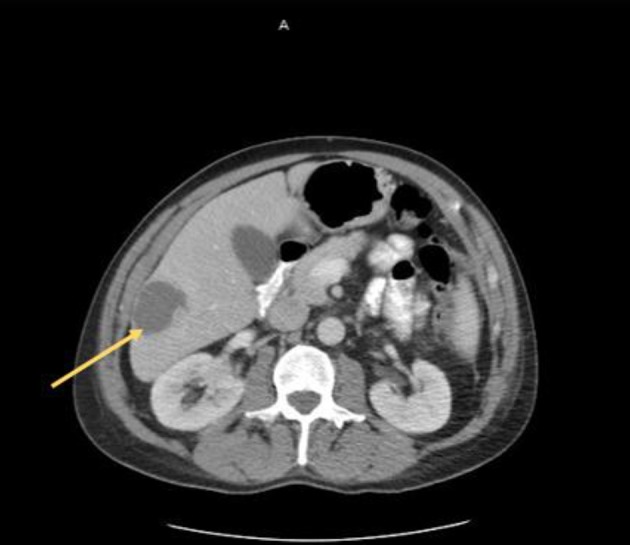

At initial presentation, his vital signs were as follows: blood pressure: 120/68 mm Hg; heart rate: 101 beats per minute; respiratory rate: 18/min; body temperature: 37.8 °C; oxygen saturation: 95% room air. Physical examination demonstrated mild tenderness in the right upper quadrant and right flank area. The patient did not have lymphadenopathy, masses or hepatosplenomegaly. On initial complete blood cell count, the white blood cell count was 13,000/µL (range: 4,500 - 11,000/µL). In addition, complete metabolic panel showed an elevated aspartate aminotransferase of 98 IU/L (range: 10 - 42 IU/L), alanine aminotransferase of 109 IU/L (range: 10 - 60 IU/L), alkaline phosphatase of 219 IU/L (range: 38 - 126 IU/L) and total bilirubin 2.6 mg/dL (range: 0.2 - 1.3 mg/dL). Hepatitis panel was negative. His erythrocyte sedimentation rate (ESR) and C-reactive protein (CRP) levels were elevated, 34 mm/h and 25.98 mg/dL, respectively. Blood and urine cultures were obtained. The patient was sent for right upper quadrant abdominal ultrasound which showed a heterogenous nodular liver with two complex masses in the right lobe, measuring 4.0 × 4.0 cm and 3.6 × 3.6 cm. The patient was started on intravenous (IV) piperacillin/tazobactam for empiric coverage. Subsequent computed tomography (CT) of the abdomen and pelvis with IV contrast revealed multiple low-attenuation lesions involving the entire right hepatic lobe, suspicious for hepatic abscesses versus cystic metastases. The largest lesion involved the inferolateral aspect of the right lobe, measuring 4.2 cm in greatest diameter (Fig. 1). A notable 4.0 × 5.7 cm small bowel mesenteric mass was also identified on imaging (Fig. 2). After discussion with the patient, surgical exploration with liver biopsy was planned.

Figure 1.

Liver lesion (arrow) identified on axial CT scan of the abdomen and pelvis. CT: computed tomography.